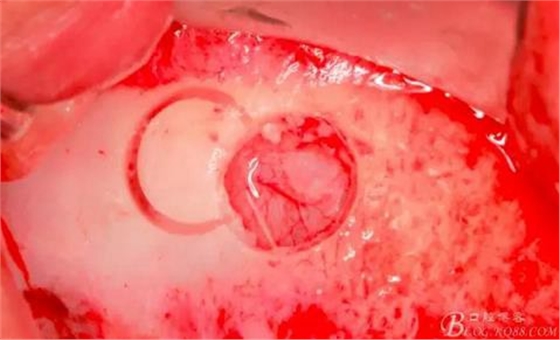

連接水壓系統(tǒng)(工具盒里的橡皮塞是無色透明的)。

用橡皮塞完全封閉洞口注入1-2mml水。

此時(shí)頰側(cè)竇膜與骨壁已經(jīng)分離,無需擔(dān)心開窗損傷竇膜。使用環(huán)切鉆以小洞口為中心開窗,轉(zhuǎn)速500轉(zhuǎn),為了保證安全,可以將種植機(jī)調(diào)成反轉(zhuǎn)模式,一樣有強(qiáng)大的切割效率。